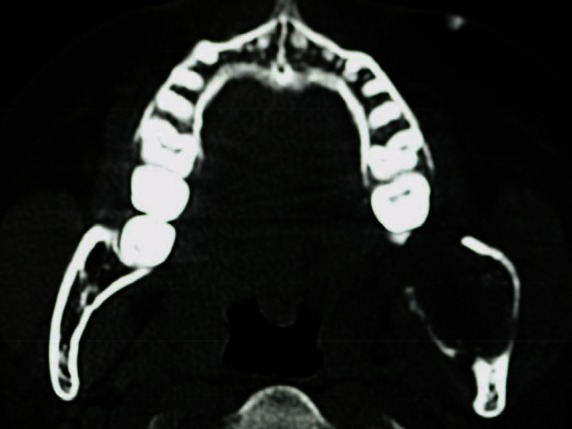

An orthopantomogram demonstrated a multilocular radiolucent lesion with sclerotic margin, which extended from the distal root of the lower left first molar to the sigmoid notch of the ascending ramus of the left mandible (Figure 3). On the postero-anterior (PA) view, the lesion showed marked radiolucency in the left posterior mandible. The computerized tomography (CT) scan also suggested expansion and thinning of both the buccal and lingual cortical plates (Figure 4). Based on the history and clinical as well as radiographic examination, a provisional diagnosis of OKC, ameloblastoma, ameloblastic fibroma, intraosseous mucoepidermoid carcinoma was given.

Figure 4: CT scan showing expansion and perforation of buccal and lingual cortical plates.

In OKCs, there is almost non or very little expansion seen in the cortical plates on axial CT scan view [12]. But in our case, on CT, intraosseous carcinomas usually showed an extensive buccolingual expansion of cortical plates [25, 26]. The probability of a malignant lesion is due to the presence of lingual expansion [26] as well as jagged or irregular margins with indistinct borders, which was seen in our case. Therefore, when such a lesion is asymptomatic and casually discovered, one should correlate with the radiographic features of malignancy.